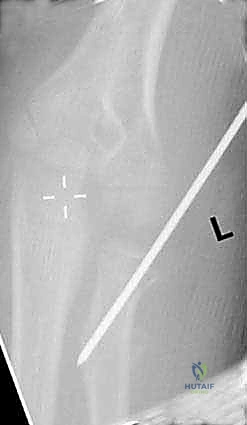

2. تقنية الرد عبر الجلد باستخدام عصا التحكم (Percutaneous Joystick Technique)

إذا لم تنجح تقنية المسامير النخاعية وحدها، يستخدم د. هطيف هذه التقنية المتقدمة.

* يتم إدخال سلك معدني رفيع (K-wire) عبر الجلد مباشرة إلى رأس الكعبرة المكسور.

* يُستخدم هذا السلك كـ "عصا تحكم" (Joystick) لتوجيه وتدوير رأس الكعبرة وإعادته إلى مكانه بدقة متناهية.

* بعد الرد، يمكن تثبيت الكسر باستخدام أسلاك تعبر موقع الكسر مؤقتاً، وتُزال بعد التئام العظم.

استخدام سلك معدني (K-wire) كعصا تحكم لتوجيه رأس الكعبرة المكسور بدقة متناهية.